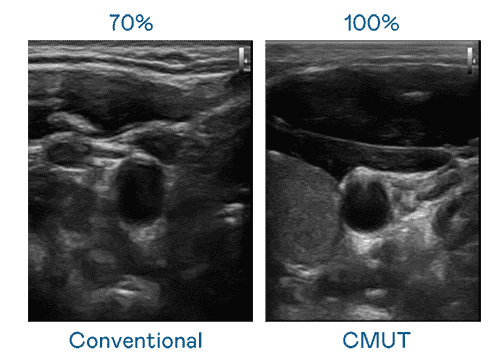

CMUT 技术是一种用电容式微机电元件来产生超音波讯号的技术。。与传统 PZT 压电式技术相比,,,,CMUT 频宽增加 30%,,更宽频的超音波讯号让影像解析度大幅提升,,,,是实现高影像品质医疗超音波扫描、、、促进精准医疗发展的关键技术。。

大频宽带来超清晰影像

超音波影像的解析度高低,,,首先取决于探头能发出的讯号频宽。。918.COM CMUT 可提供高清晰的超音波讯号,,,,提供高频宽、、、高灵敏度、、、、影像纹理细节更高的超音波影像,,,,协助医护人员缩短影像判读时间及利用精准的医疗影像进行诊断。。